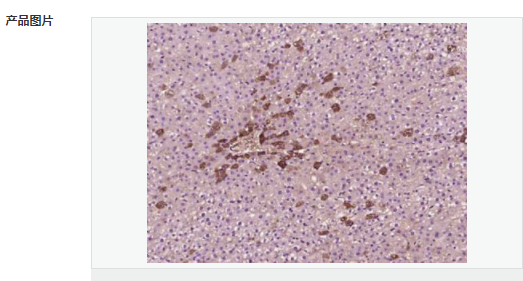

交叉反應(yīng):Human,Mouse,Rat(predicted:Phosphotyrosine) 推薦應(yīng)用:IHC-P,IHC-F,ICC,IF

| 產(chǎn)品應(yīng)用 | IHC-P=1:100-500 IHC-F=1:100-500 ICC=1:100-500 IF=1:100-500 (石蠟切片需做抗原修復(fù)) not yet tested in other applications. optimal dilutions/concentrations should be determined by the end user. |

| 產(chǎn)品介紹 | The phosphorylation of specific tyrosine residues has been shown to be a primary mechanism of signal transduction during normal mitogenesis, cell cycle progression and oncogenic transformation, its role in other areas such as differentiation and gap junction communication, is a matter of active and ongoing research. Antibodies that specifically recognize phosphorylated tyrosine residues have proved to be invaluable to the study of tyrosine phosphorylated proteins and the biochemical pathways in which they function. SWISS: N/A CAS: 21820-51-9 Important Note: This product as supplied is intended for research use only, not for use in human, therapeutic or diagnostic applications. |